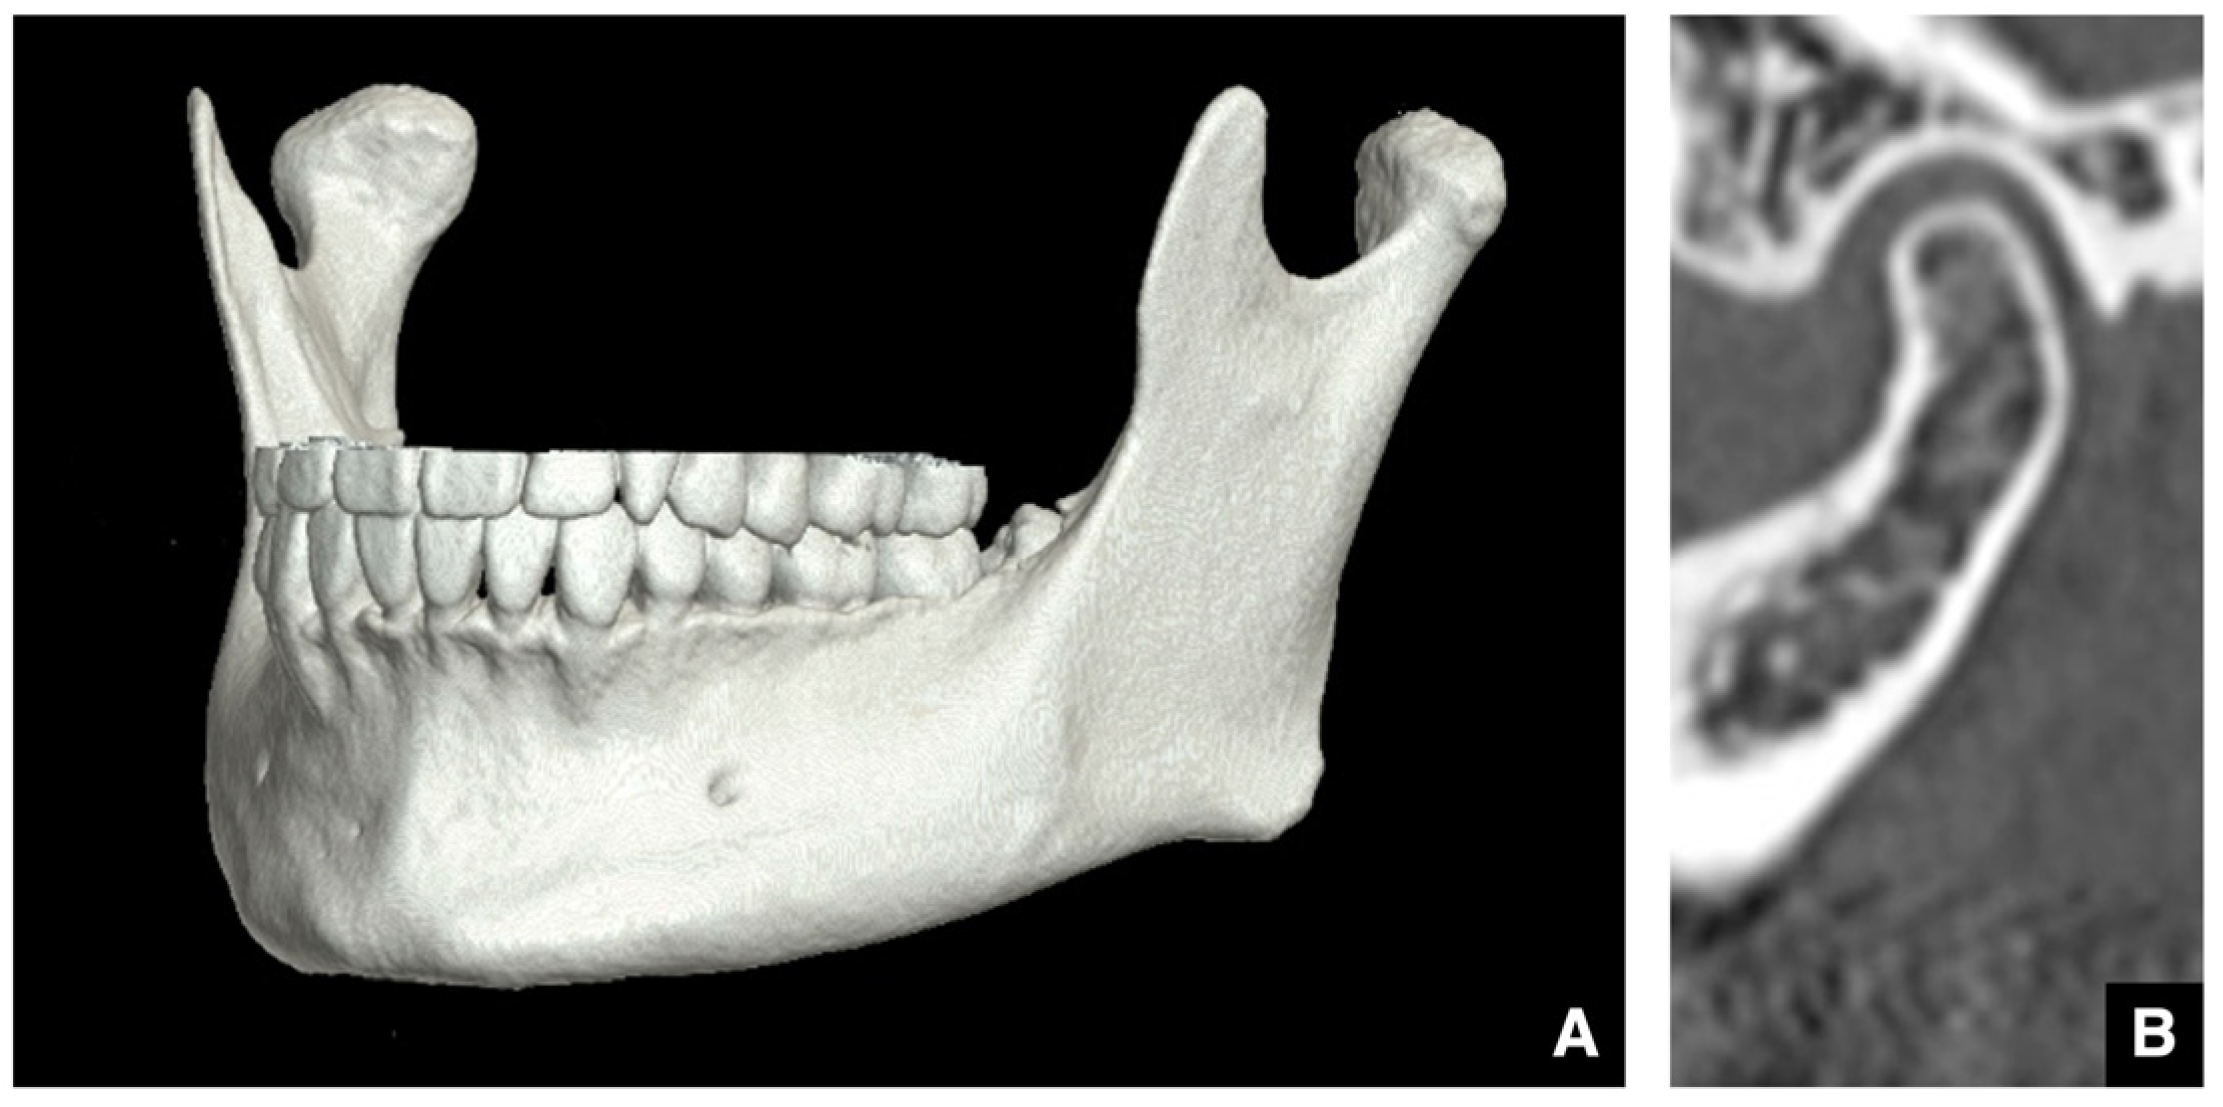

| Enhanced safety through improved visibility 1. Course of the submental artery and its branches Identification of the submandibular gland and its medial aspect 2. Course of the sublingual artery and the mental nerve Identification of the mentalis muscle, hyoglossus muscle, and anterior belly of the digastric muscle and their medial aspects (Observed within the fatty tissue beneath the chin) 3. Course of small blood vessels along the bone surface Degree of looping at the mentum foramen during opening, course of the incisive branch Setting the osteotomy line 1. Position of the mental foramen and course of the incisive branch Record the position of each root for each lower tooth 2. Position of the mandibular anterior tooth roots Record the thickness of the cortical bone using the mandibular teeth as a reference point 3. Variation in cortical bone thickness in the anterior mandible Depression of the cortical bone in the mandibular anterior region, trabecular bone defect |